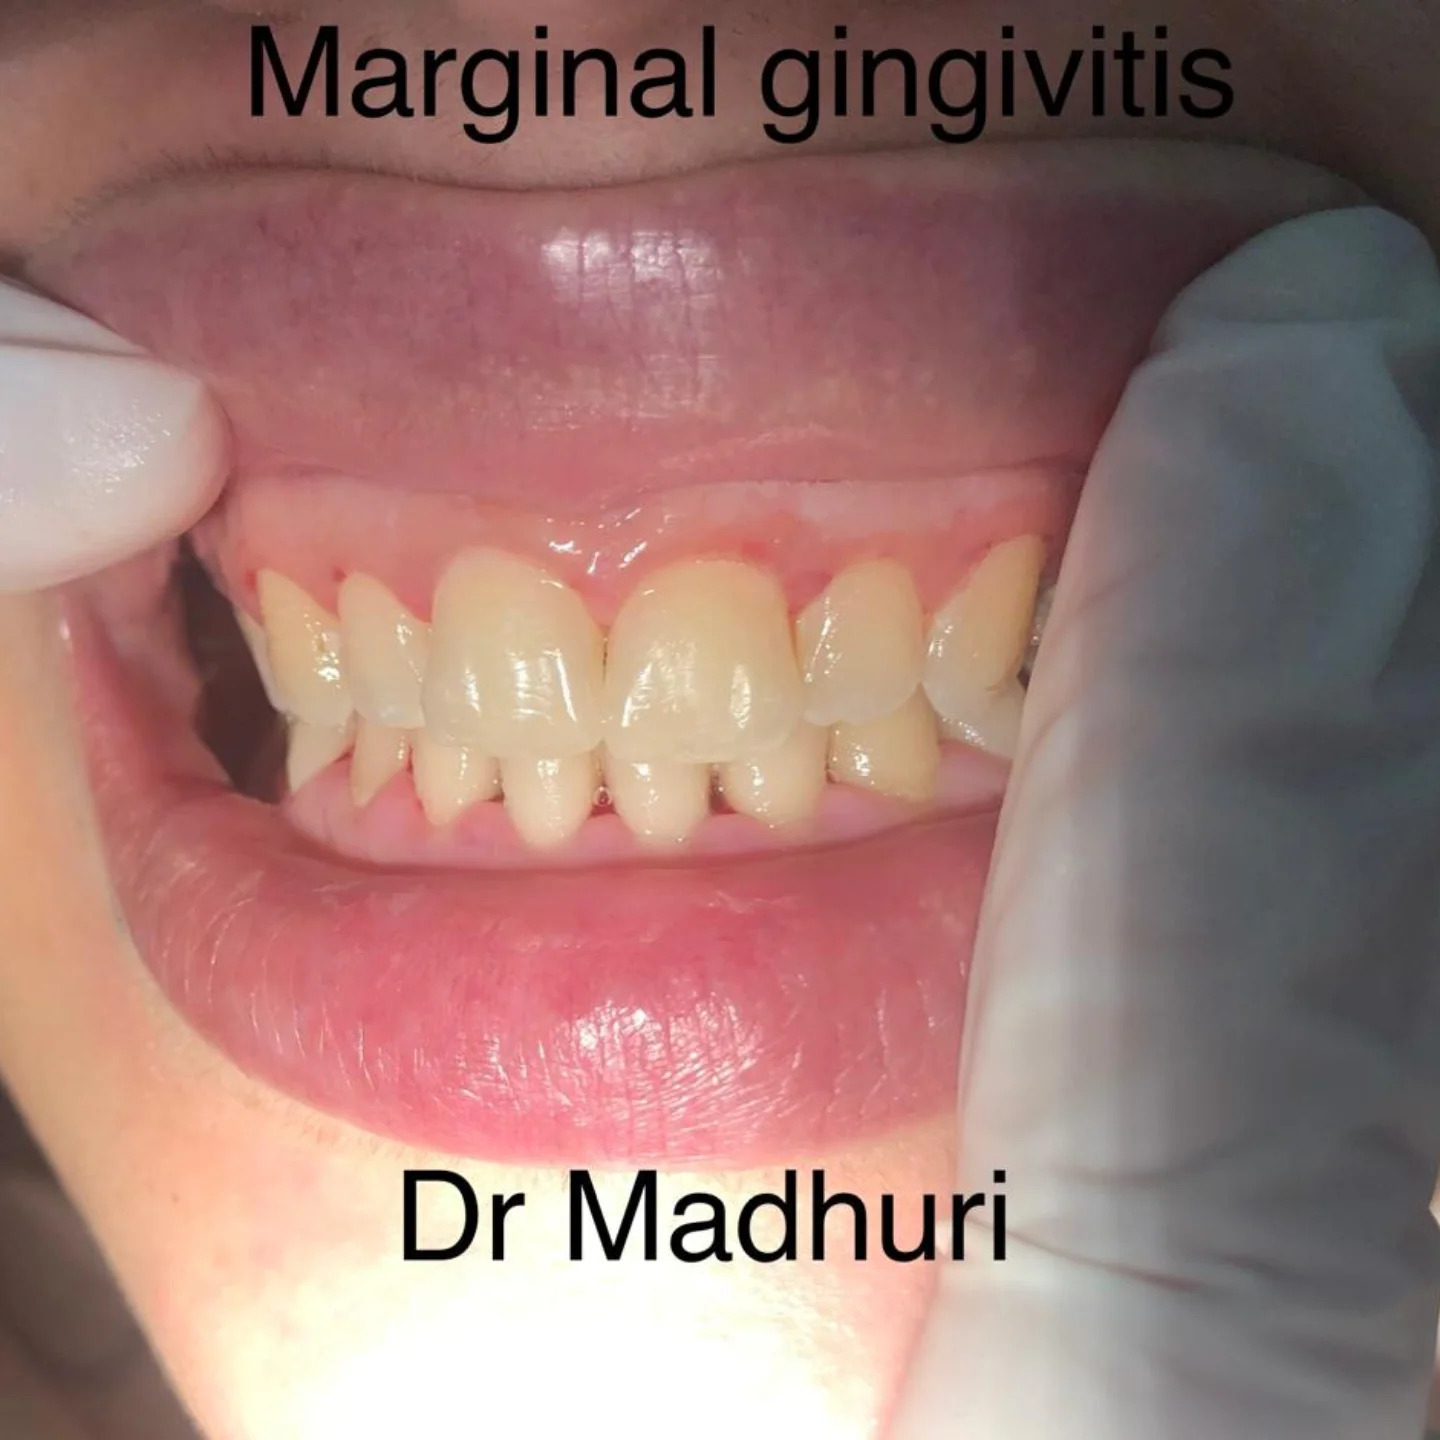

Explore Our Clinical Dental Gallery

Welcome to our official treatment gallery, showcasing the real results, smile transformations, and advanced dental care delivered by Dr. Madhuri. We believe that a picture is worth a thousand words when it comes to the art and precision of modern dentistry. Review our comprehensive visual portfolio below to see how our dedicated care helps patients achieve healthy, beautiful, and confident smiles.